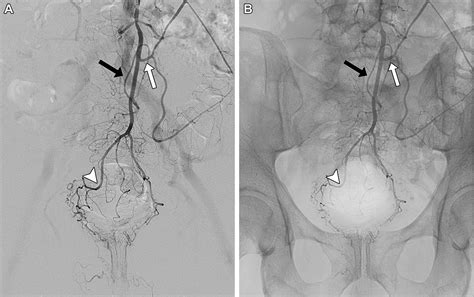

Hemorrhoid Artery Embolization is a cutting-edge, image-guided procedure performed by interventional radiologists. Unlike traditional surgery, which physically removes the hemorrhoidal tissue, HAE works by targeting the blood supply that feeds the hemorrhoids. By reducing the arterial blood flow to the hemorrhoidal plexus, the procedure causes the hemorrhoids to shrink over time, effectively alleviating symptoms like bleeding, pain, and protrusion.

Because it is a minimally invasive technique, it does not require general anesthesia or incisions in the sensitive anal region. Instead, a tiny catheter is guided through a blood vessel in the wrist or groin to the specific arteries supplying the hemorrhoids. Small particles are then injected to block these vessels, successfully reducing the pressure and engorgement of the hemorrhoidal tissues.

2. Guidance: Using real-time X-ray imaging (fluoroscopy), the radiologist navigates a microcatheter through the vascular system.

3. Embolization: Once the specific hemorrhoidal arteries are identified, specialized embolic agents are injected to reduce the blood supply.